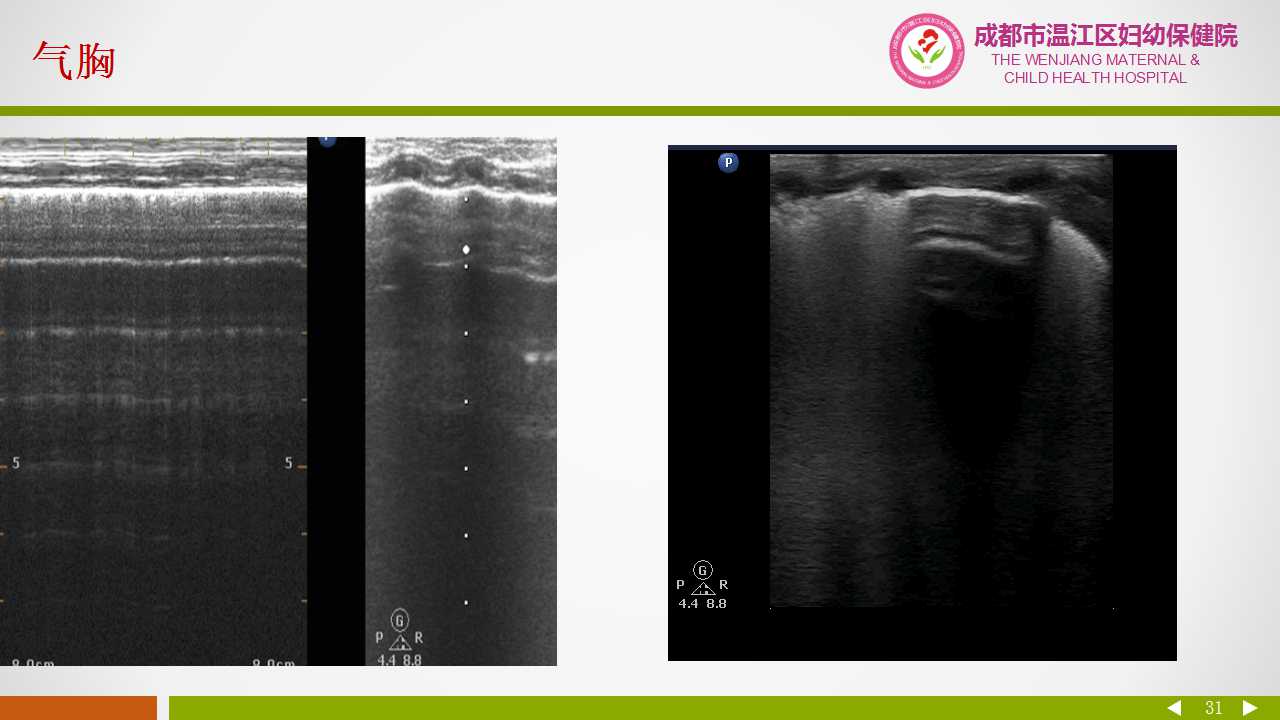

小儿肺超声诊断技术

三、项目介绍